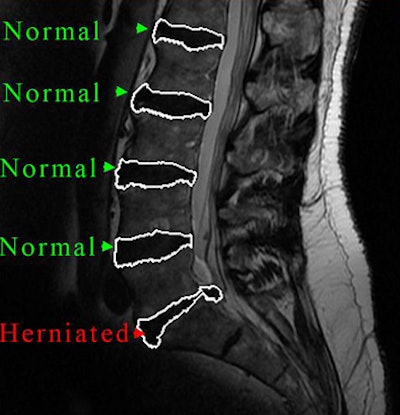

| CAD segments the intervertebral disk material (right) from T2-weighted MR images. |

The CAD's sensitivity for detecting a herniated disk was 93%, with a specificity of 83%. The area under the receiver operator characteristics curve was 92%; agreement with the radiologist not using CAD was 69%.

| CAD output distinguishes normal from herniated lumbar disks. |

Measurement repeatability rose to an intraclass correlation coefficient greater than 0.97 using the method, and both regional features and co-occurrence textural features showed statistically significant differences between normal and herniated disks (p < 0.001).